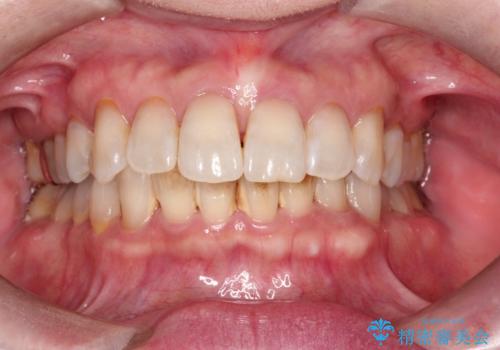

歯についたタバコのヤニをPMTCで綺麗に

- 電子タバコを吸う習慣があり、ステインがついてしまっている見た目が気になるとのことで来院されました。ステインだけではなく、歯石も全体的に付着していたためPMTC60分コースを行いました。